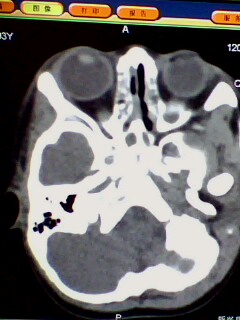

标题: PED3023:鼻咽增殖体肥大。

男,3岁小儿,经常睡觉时张口呼吸、打鼾。

1、鼻咽增殖体肥大继发左侧乳窦炎?

2、双侧上颌窦炎?

1、左侧乳窦气房硬化型改变,是发育不完全还是鼻咽增殖体肥大阻塞咽鼓管开口引起中耳炎?

2、双上颌窦应该有炎症了吧,听好多人说,小孩副鼻窦还没发育完全也可有这种表现,究竟两者怎样鉴别?请各位战友指点。多谢